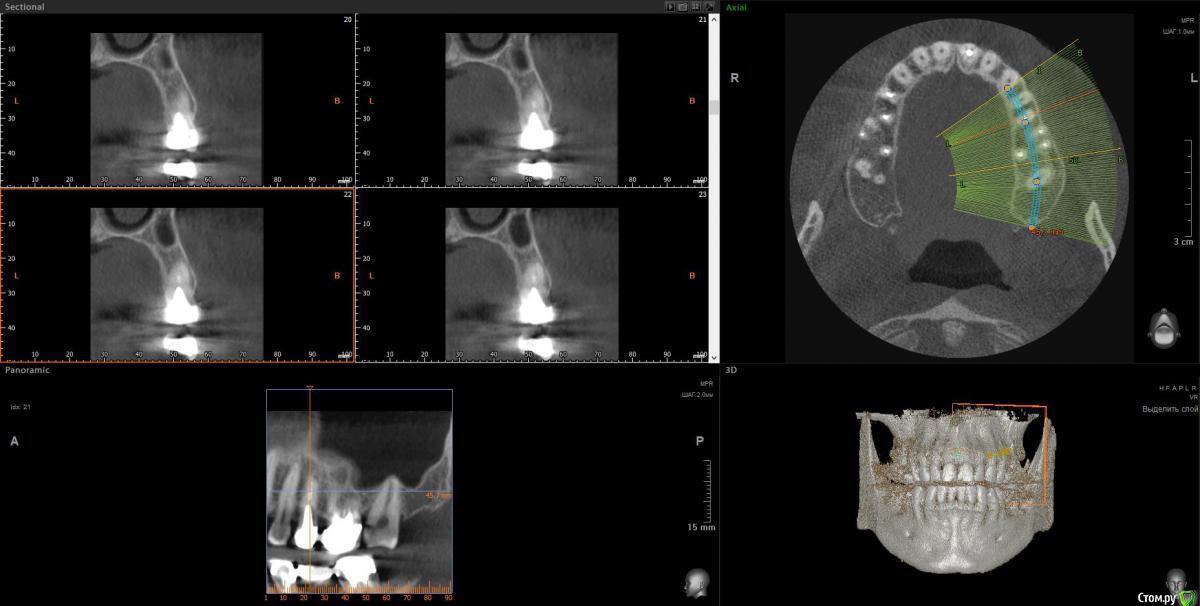

wladdX Опубликовано 12 февраля, 2018 Поделиться Опубликовано 12 февраля, 2018 Скрины 1 Ссылка на комментарий

Taurus007 Опубликовано 13 февраля, 2018 Автор Поделиться Опубликовано 13 февраля, 2018 wladdXОгромное спасибо за скриншоты. Я бы даже близко так не смог) Пришел расчет и анализ ТРГ. Заключение.pdf Ссылка на комментарий

Bier Опубликовано 22 февраля, 2018 Поделиться Опубликовано 22 февраля, 2018 Справа синуслифтинг не потребуется 100%Слева - возможно в области 26 зуба. Для оценки прикуса одного ТРГ мало, надо еще фото моделей. Вам их наверное делали? Ссылка на комментарий

Taurus007 Опубликовано 24 февраля, 2018 Автор Поделиться Опубликовано 24 февраля, 2018 Справа синуслифтинг не потребуется 100% Слева - возможно в области 26 зуба. А в целом, можно ли сейчас не трогать область, где возможно потребуется синуслифтинг, поскольку в практическом смысле это наименее проблемная область, хоть коронки и стоят уже 9 лет ? надо еще фото моделей. Вам их наверное делали? Не делали. Это как-то в домашних условиях возможно? Ссылка на комментарий